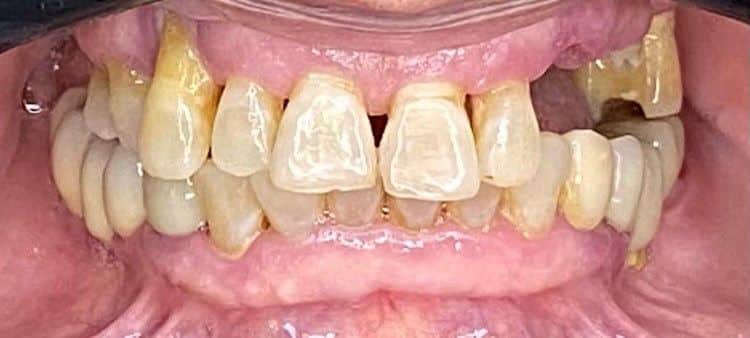

Case 005 Case: Técnica de ancoragem esquelética “All on Four STD” pelo Dr. Carlos Franza

Formado há 20 anos, o experiente Dr. Carlos Franza tem como foco de trabalho casos complexos de reabilitação total.

Atua no estado de São Paulo desde 2002 na área da implantodontia e Bucomaxilo, buscando sempre parcerias e interações de grandes profissionais da área no desenvolvimento e operacionalidade de novas técnicas buscando acima de tudo, satisfação dos pacientes.